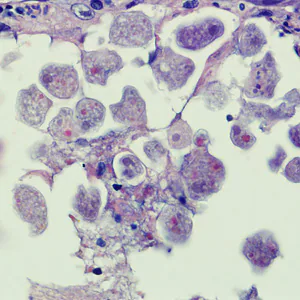

Case #258 – August, 2009

A biopsy was performed on a 23-year-old woman with no known travel history, presenting with a perianal ulcer. The specimen was preserved in formalin and sent to a pathology lab for work-up. Figures A and B show what was observed at 500x magnification from a section of the tissue, stained with hematoxylin and eosin (H&E). What is your diagnosis? Based on what criteria?

Figure B